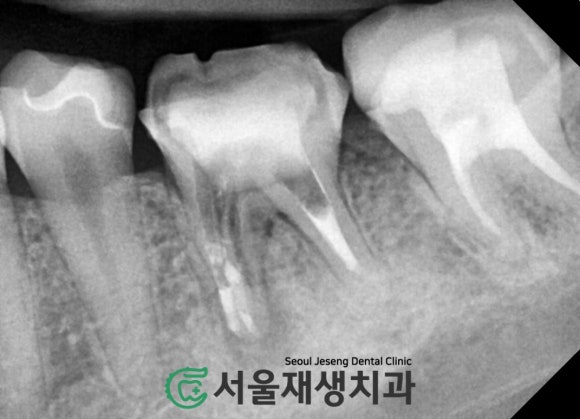

확대하여 촬영해보겠습니다.

치아 뿌리 끝에서 시작된 염증이

주위의 뼈를 녹이고 있습니다.

아하,

뿌리끝 주위로

까맣게 보이는 빈공간은

다름 아닌

염증으로 인해

뼈가 흡수된 공간이로군요!